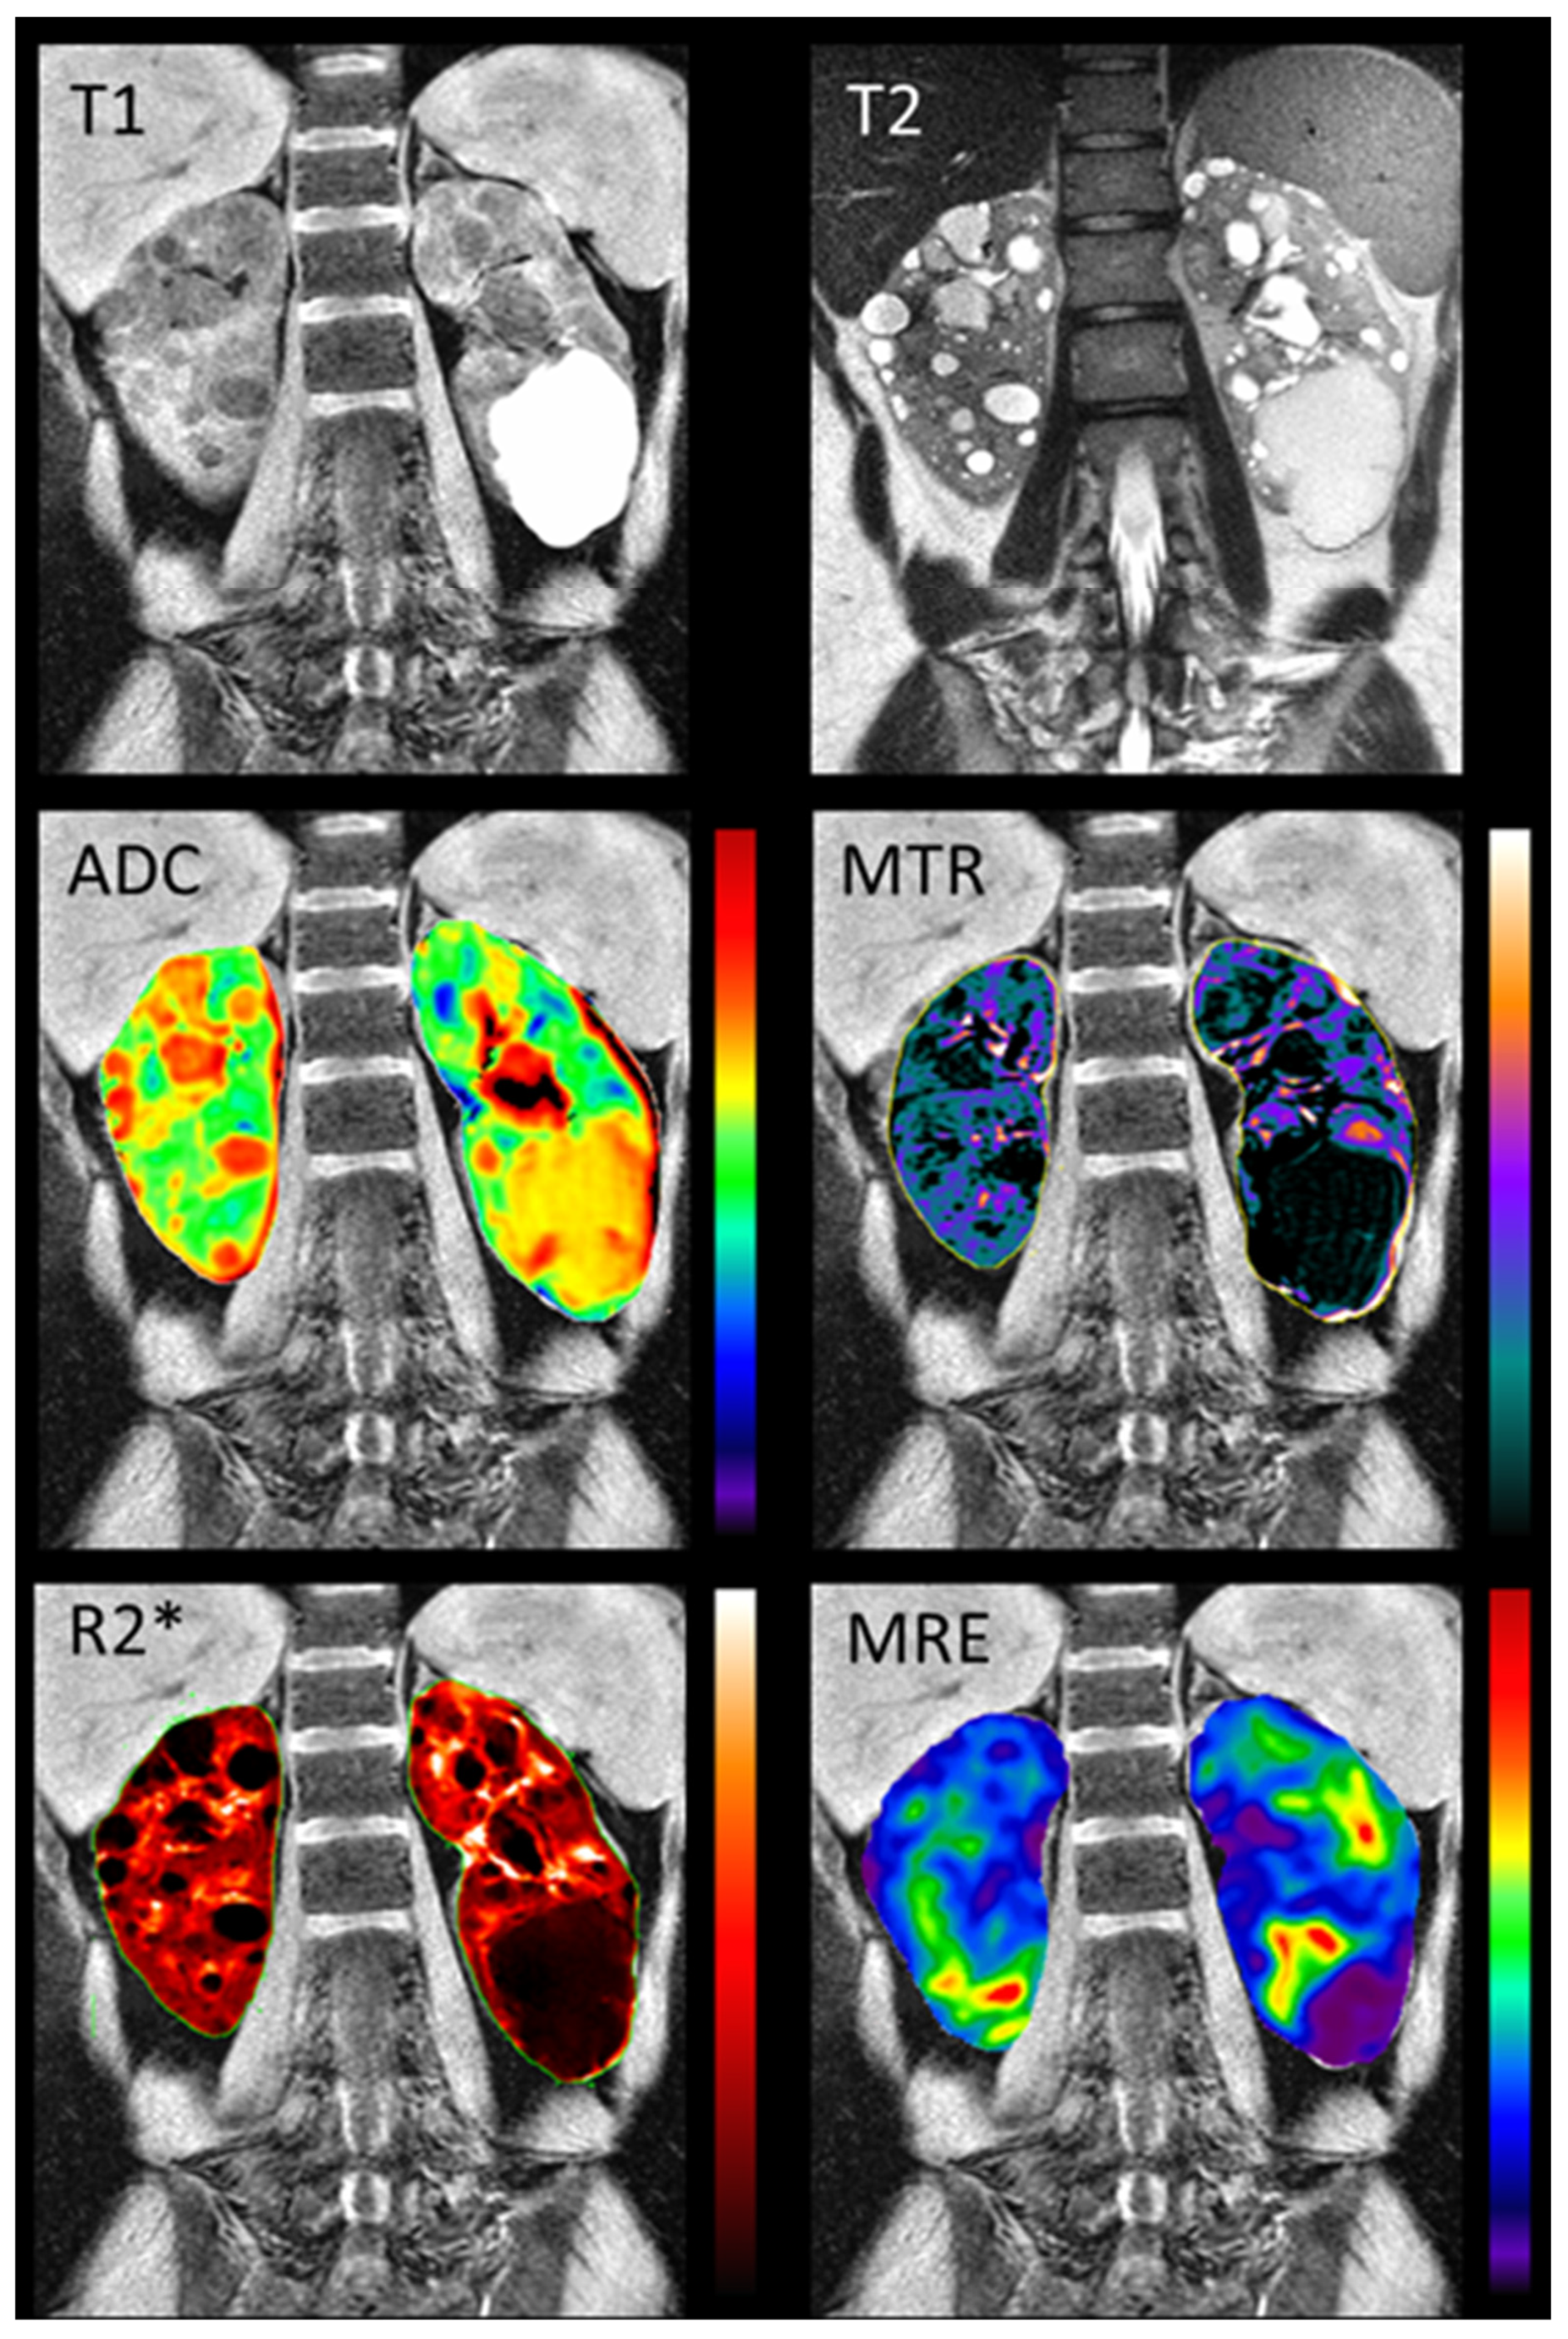

5. Multiparametric Magnetic Resonance Imaging

| MRI measure | Description |

|---|---|

| Diffusion weighted imaging (DWI) | Provides information about kidney microstructure by detecting the displacement of water molecules (Brownian motion) within the architecture of tissues.[76] |

| Phase-contrast (PC-MRI) | Measures blood flow in renal arteries.[80] |

| T1 mapping | Provides a quantitative map over the whole kidney for T1 values, informing on kidney microstructure.[81] |

| T2 mapping | Provides quantification of T2 as tissue-specific time parameter.[81] |

| Blood oxygen level dependent (BOLD) MRI | Indirectly assesses renal oxygenation, exploiting the paramagnetic properties of deoxygenated haemoglobin.[82] |

| Arterial Spin Labelling (ASL) | Measures tissue perfusion by using magnetically labelled water protons in blood.[83] |

| Magnetization transfer imaging (MTI) | Provides information about tissue composition and microstructure by measuring magnetization transfer ratio. |

| Magnetic resonance elastography (MRE) | Provides information about kidney tissue stiffness using shear waves propagating in the tissues.[84] |

| Dynamic contrast-enhanced MRI | Measures renal perfusion and provide a direct measure of GFR, although requiring administration of an exogenous contrast agent.[85] |